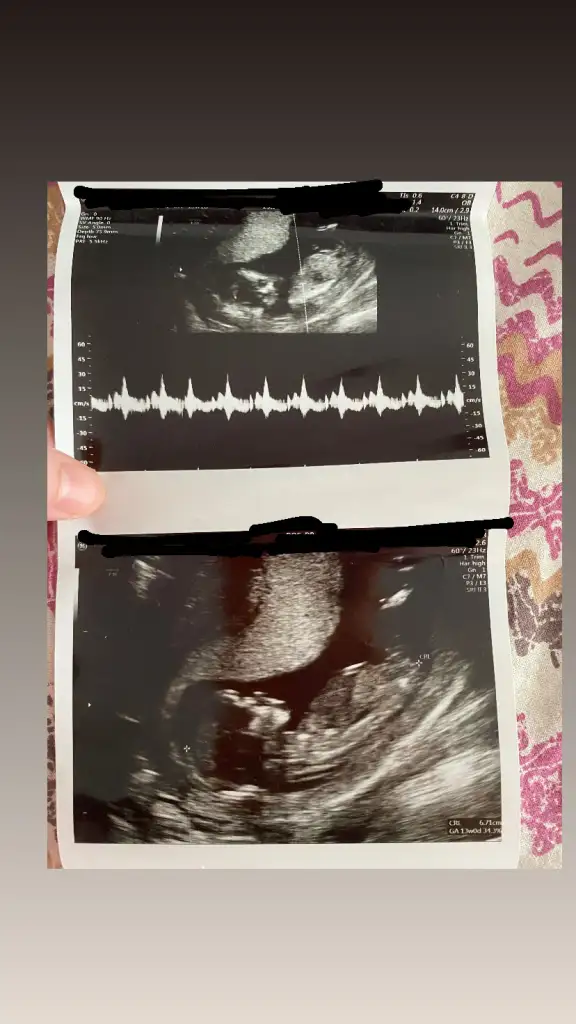

Kıza benziyor, kesenin yuvarlak olması kız fasulye tipi erkek diyorlar ona istinaden13 haftalık anlayan varmı ?

Alttaki erkek üstteki kız gibi geldi banaMerhaba kızlar cinsiyet tahmini yapabilen var mı acaba 13 haftalık ikiz gebelik birinin cinsiyeti öğrendik ama bu miniginkini doktorumuz daha var dedi. Tahminleri alayım? Eki Görüntüle 3582600